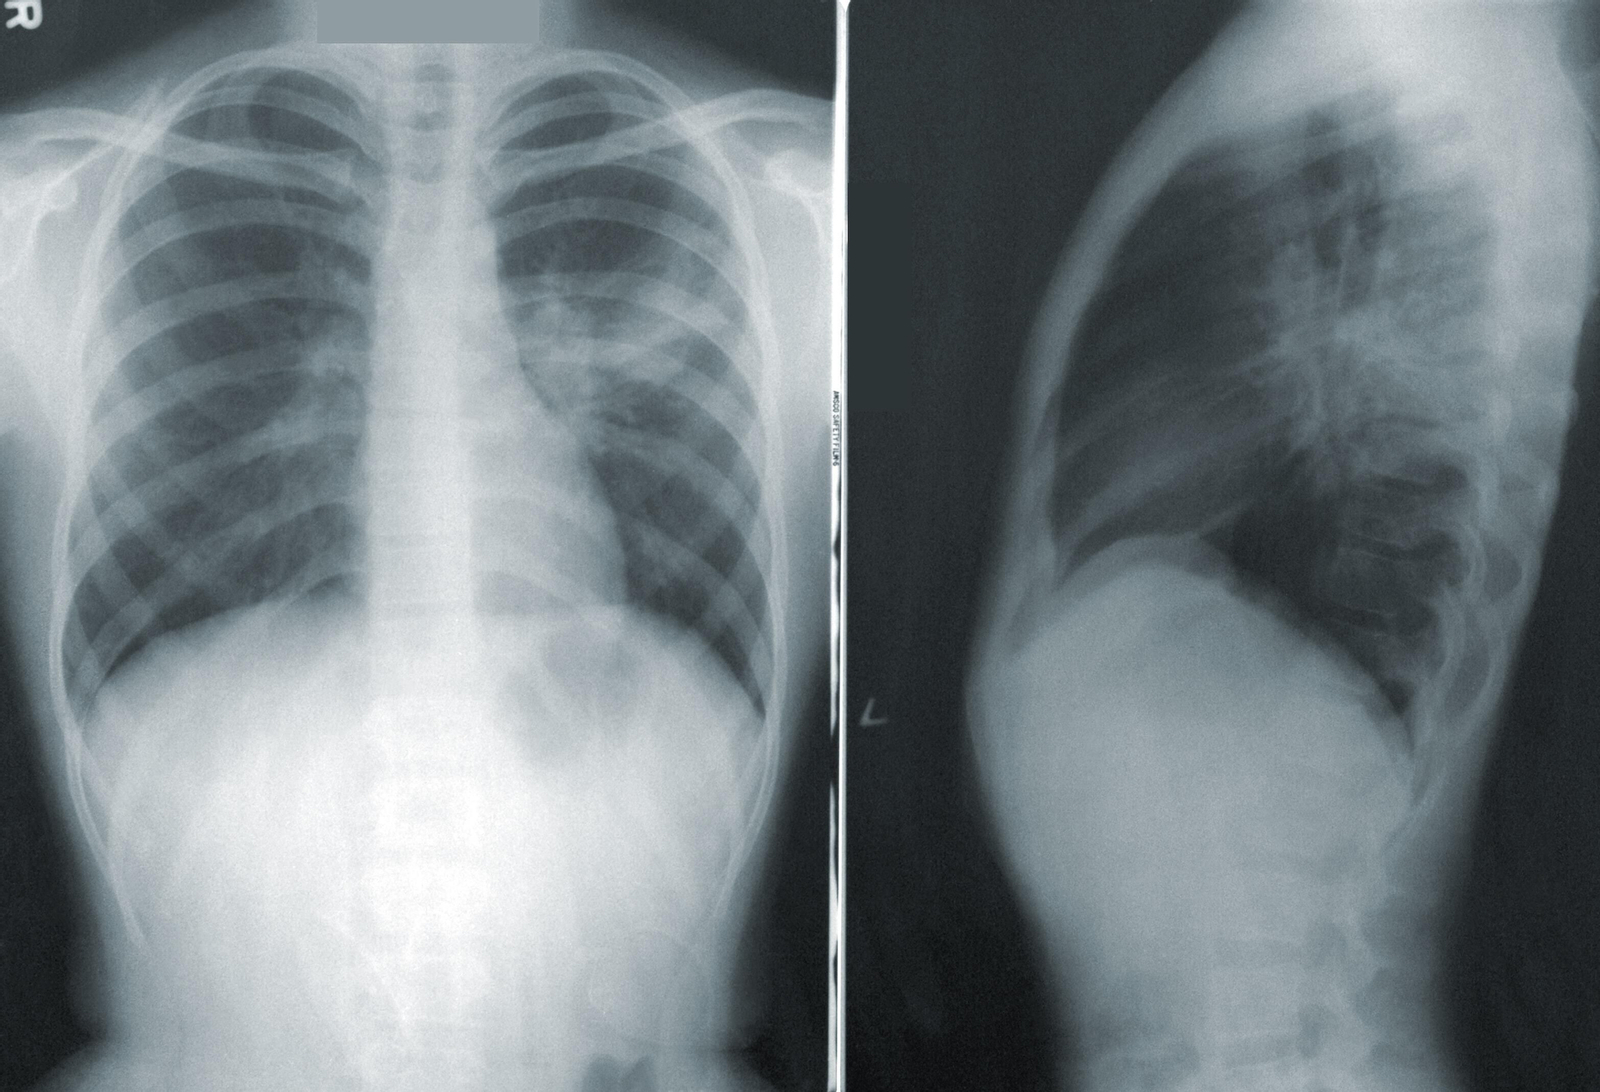

Aunque Zapatero habla de alta transmisibilidad de estas nuevas variantes, las cuales han presentado un nuevo paradigma, hace especial hincapié en que los ingresos hospitalarios "no llegan ni a 40 en toda la comunidad de Madrid". Eso sí, insiste en el papel protagonista que está teniendo la pauta de vacunación en el desarrollo de síntomas: "si bien en las personas vacunadas estamos viendo una enfermedad distinta, en los no vacunados es tan dañina como lo es la cepa original", afirma.